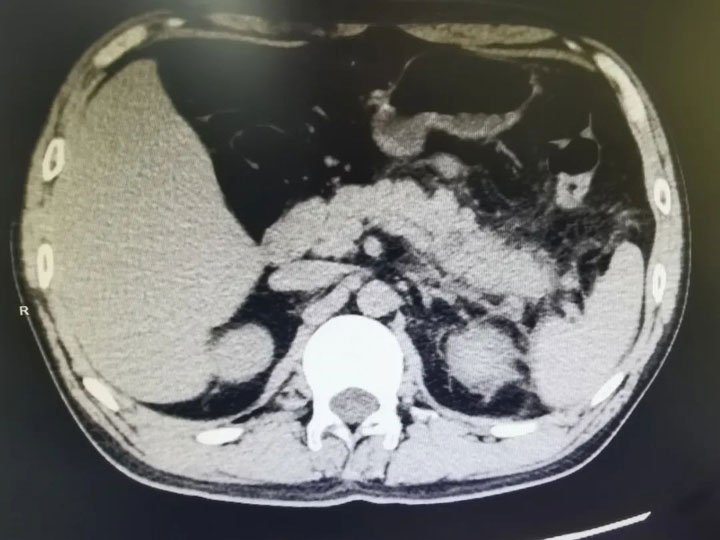

1985年男子徐某(化名)没想到,春节还没有过完,自己就因为喝酒诱发急性胰腺炎住进了医院。身高170cm,体重在80kg上下徘徊的他,一直胃口就很好,平时喜欢吃荤菜,喝酒更是不在话下。

春节期间,家人亲友相聚,一杯又一杯,一顿又一顿。年初七徐某开始觉得腹部疼痛难忍,从上腹部逐渐蔓延到整个腹部,还有恶心呕吐。

第二天凌晨,疼痛没有缓解,在家人的陪伴下他来到广济医院急诊科,被确诊为“急性胰腺炎”。

徐某被紧急收治,在普外科专家团队的精心救治下,徐某的病情得到及时控制,出现好转。普外科副主任代坤建议:“患者之前多次因胰腺炎入院,有高脂血症、长期酗酒史、脂肪肝,后续要戒酒、控制饮食、减重,可定期前往内分泌科随访血脂的变化。”